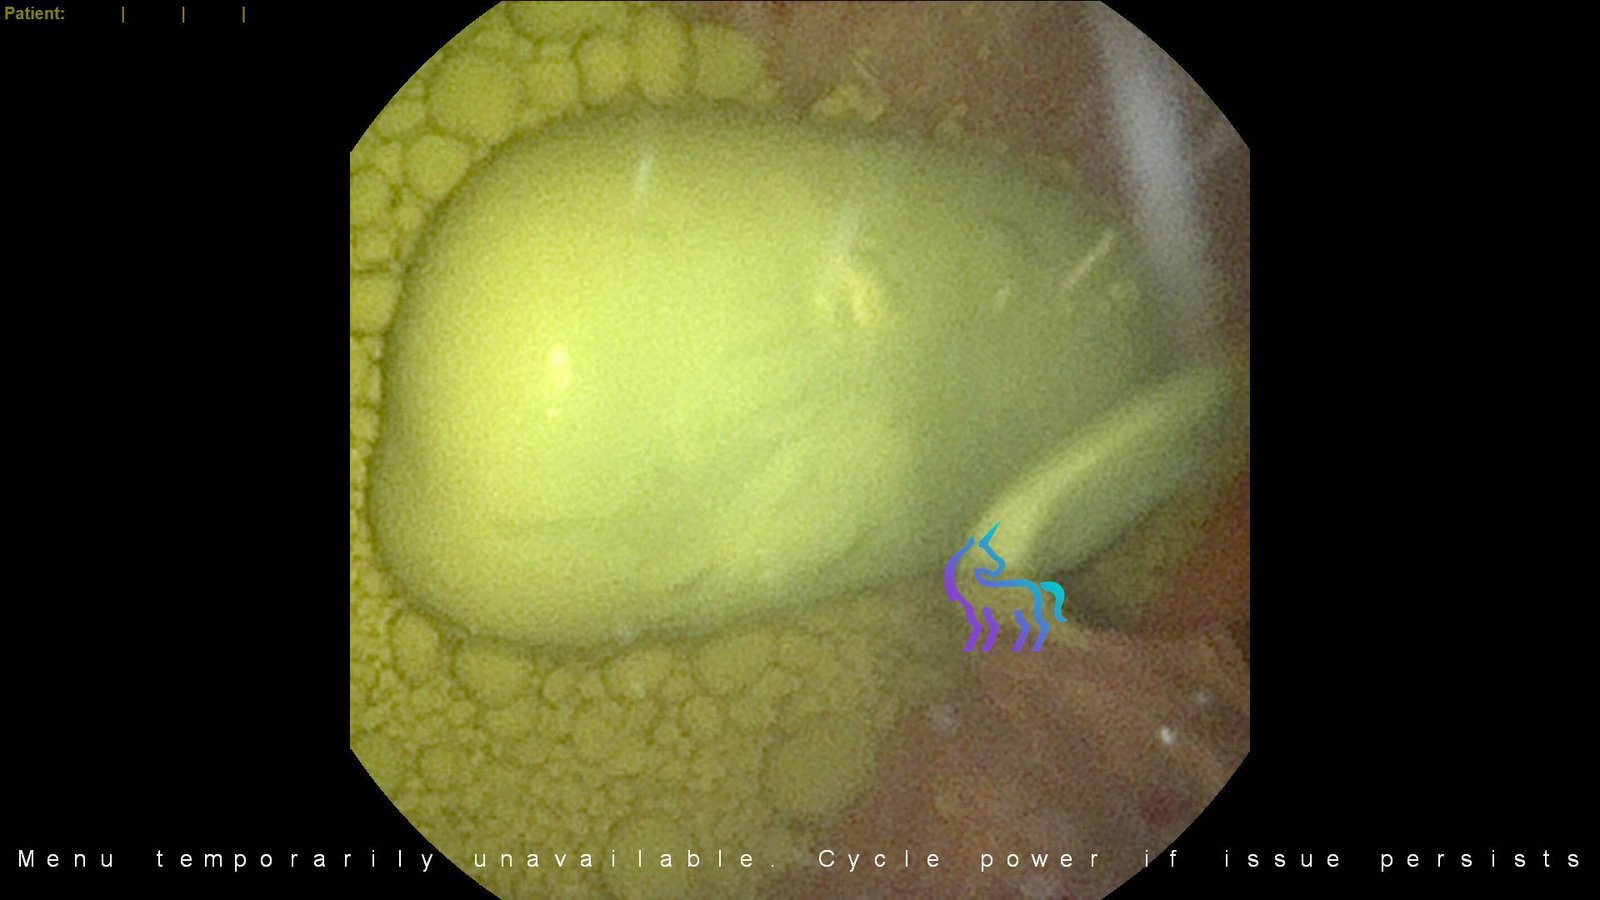

Leishmania infantum

L’histoire de la capture parasitaire et de l’expansion intercontinentale silencieuse de l’Europe vers l’Amérique.